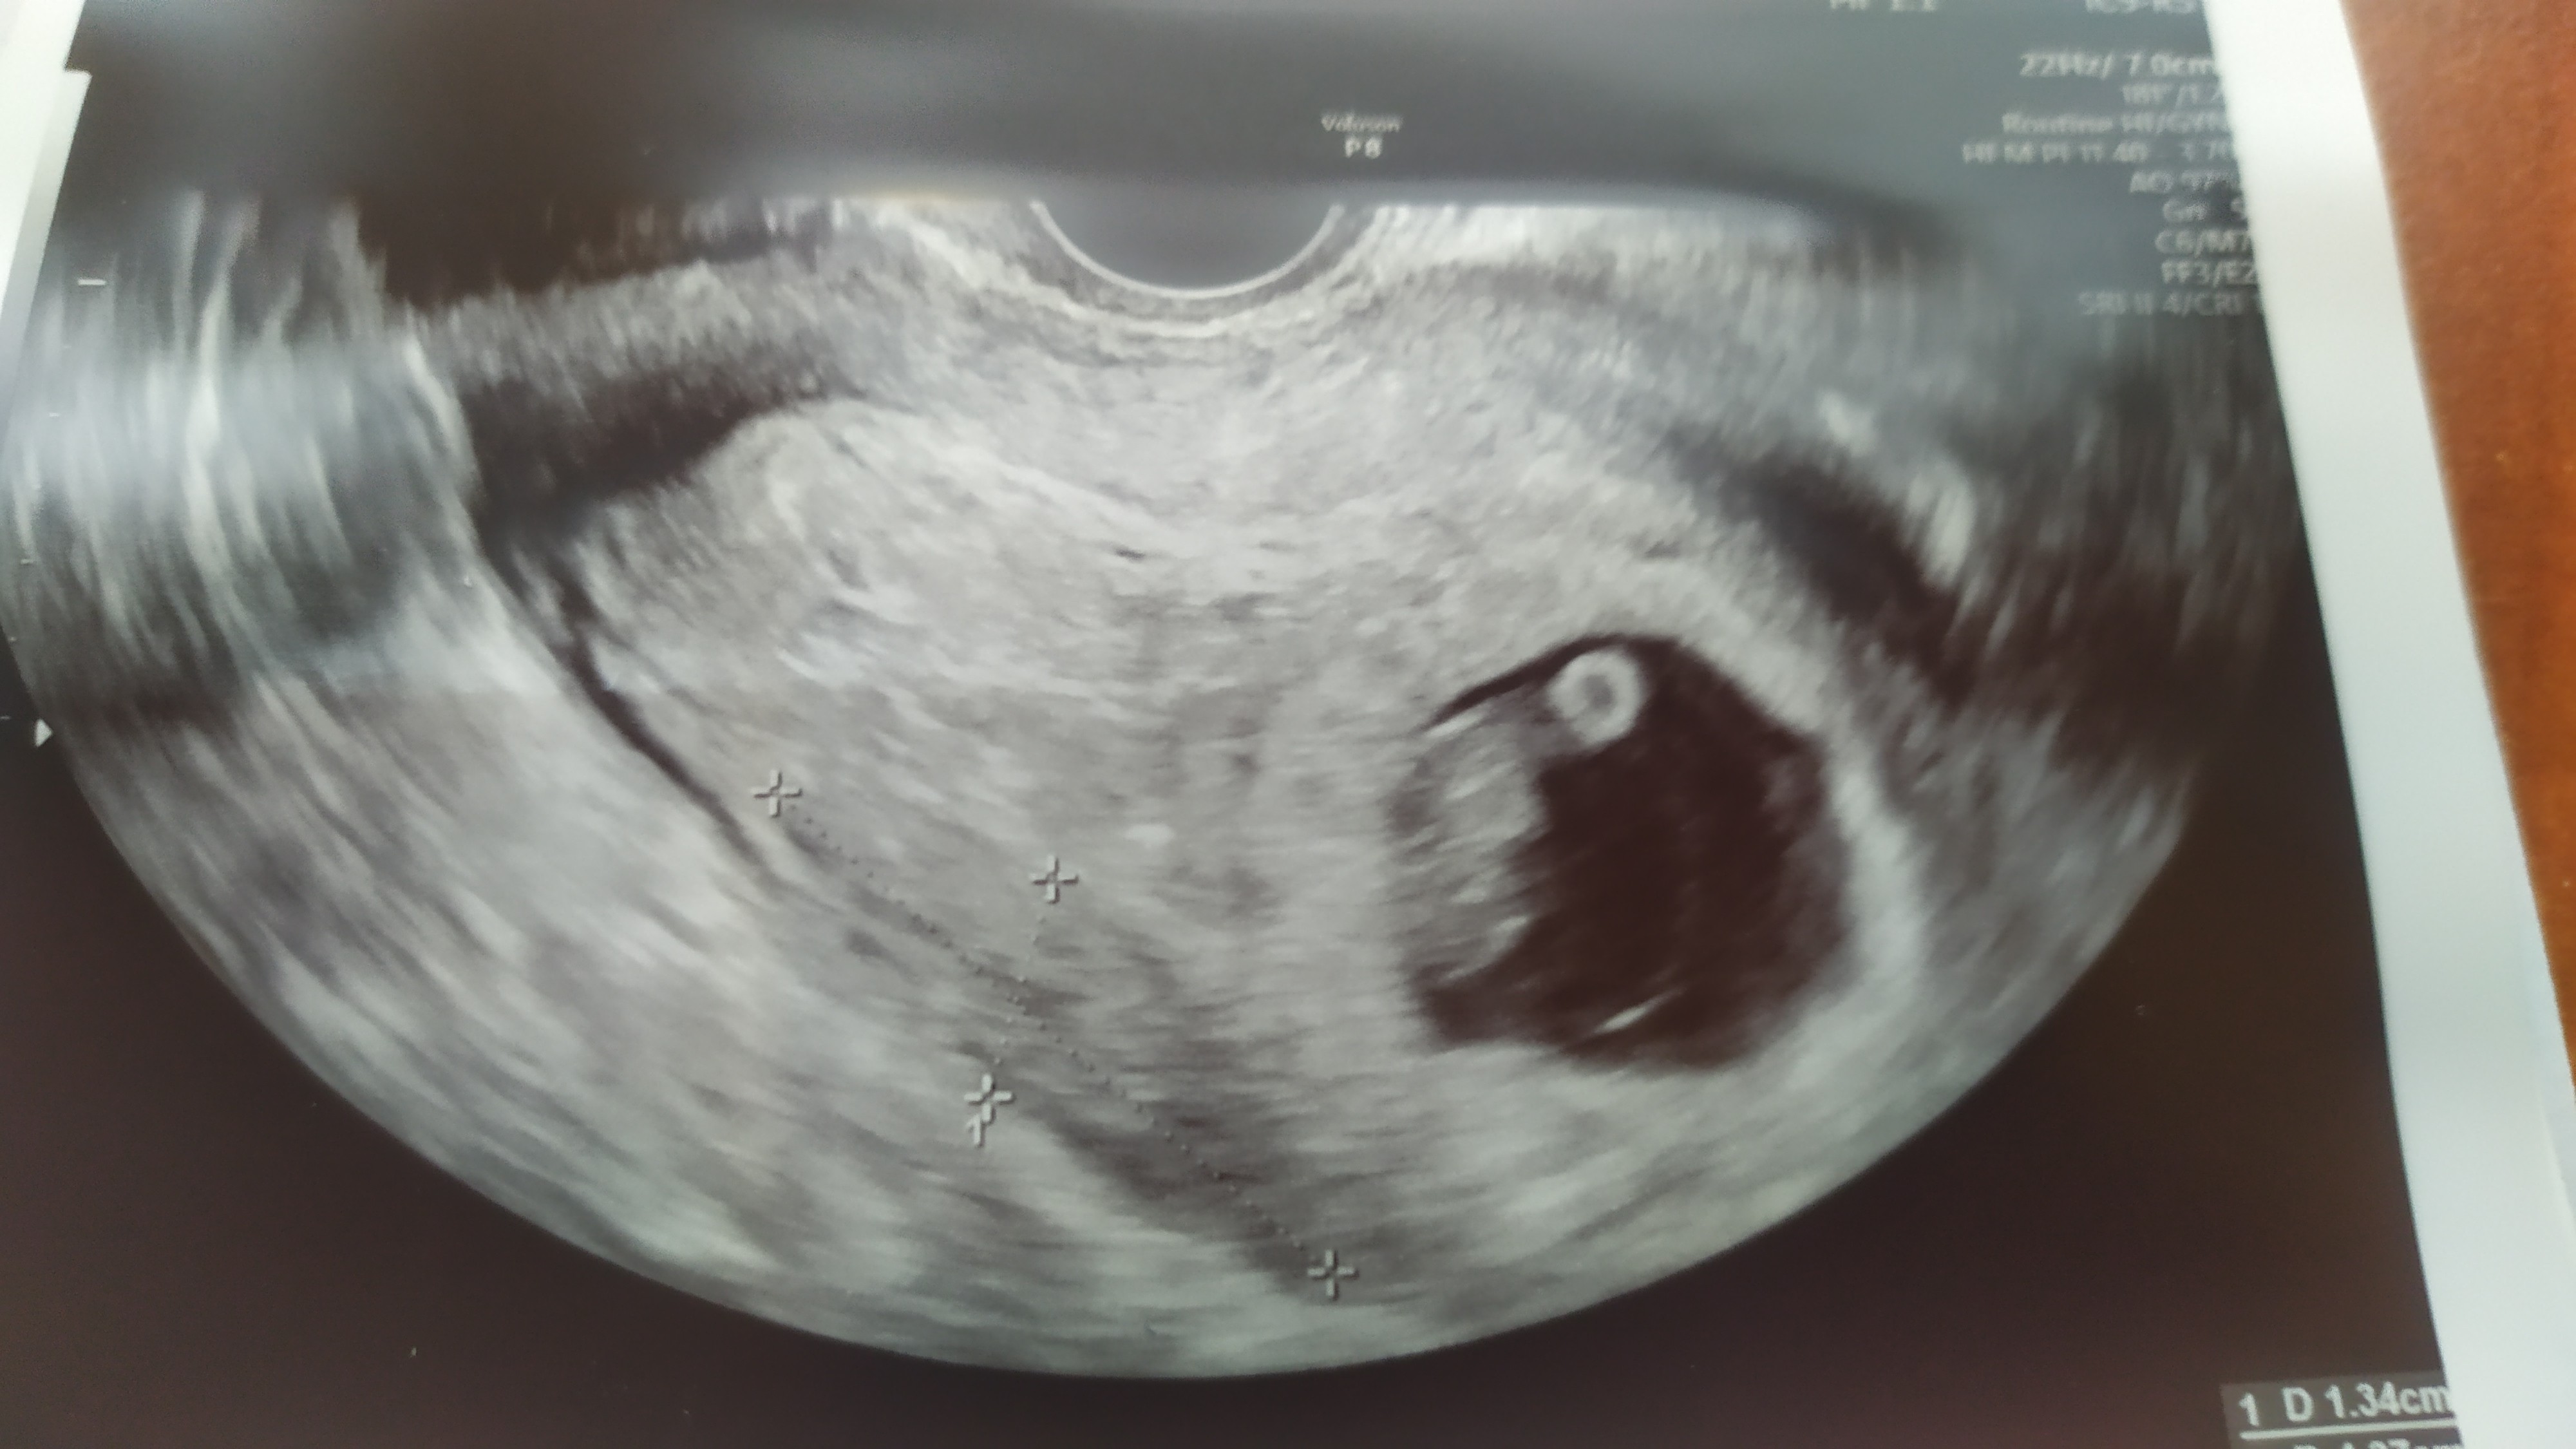

Nie wiem czy umiem zamieścić tu posta-już próbowałam i zniknął...Już po wizycie i znów mętlik w głowie...dla przypomnienia 2 tyg temu lekarka robiąc USG ciąży 6 tyg. napisała w opisie, że ciąża nieprawidłowa gdyż widoczny mały zarodek ale brak pęcherzyka żółtkowego... Dziś poszłam potwierdzić diagnozę - już do innej lekarki i zwrot - zarodek pomimo, że ciąża z OM ma 7+6 na USG ma 8+6, słyszałam serduszko ❤️tyle, że - aby nie było za dobrze lekarka powiedziała że jest krwiak którego wcześniej nie było 😔nazwany krwiak przykosmowkowy, w opisie jest też odwarstwienie kosmówki 13x43mm....mam prośbę - możecie mi coś powiedzieć ad takiego krwiaka- czy rokowania są złe?

Załączniki

• IMG_20210112_150431.jpg

IMG_20210112_150431.jpg

1 006,8 KB · Wyświetleń: 113

• IMG_20210112_150453.jpg

IMG_20210112_150453.jpg

756,8 KB · Wyświetleń: 93